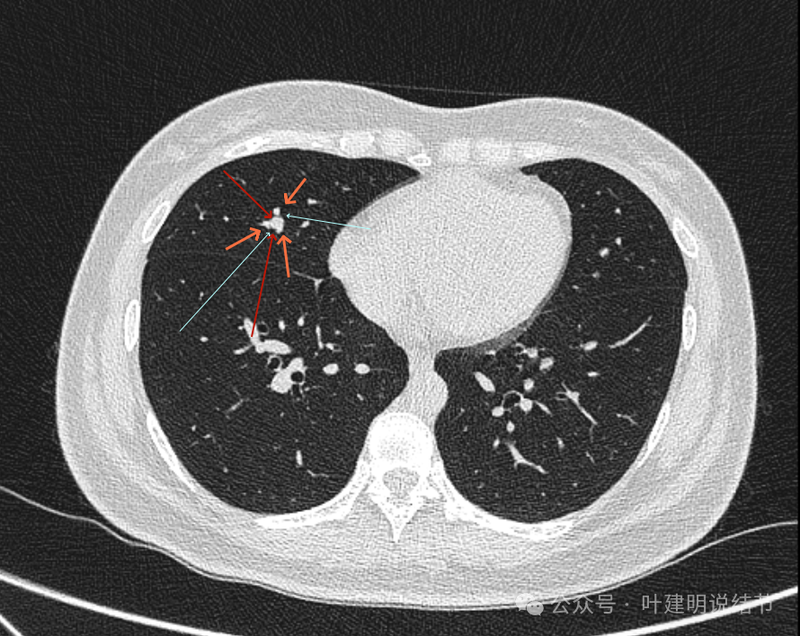

桔色的是血管,红色的是病灶,两者之间有间隙仍用天蓝色细线标注。

紧挨但仍有缝隙的。

血管贴着病灶,病灶表面略有毛糙之处。

血管有形成轻微血管弯征,两者紧贴。

两支血管夹着病灶,密度不同,有低密度间隙。

病灶与两侧血管关系均密切,明显觉得密度是不一样的,血管的密度略高,结节的略低。

病赤与血管在蓝色箭头处失去间隙,像是侵蚀血管壁,造成血管受侵犯破坏。病灶是软组织密度的,而且整体看有膨胀感。

病灶密度稍不均。表面不光滑。

病灶与边上血管间隙不清。

桔色箭头所示的血管受压稍有移位。

密度不同,关系密切。

边缘区域也是有膨胀感。

血管与病灶脱开后的样子。

边缘区也是基本上实性的。